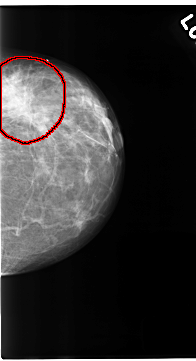

C_0123_1.RIGHT_MLO

FILE: C_0123_1.LEFT_MLO.OVERLAY

TOTAL_ABNORMALITIES 1

ABNORMALITY 1

LESION_TYPE MASS SHAPE IRREGULAR MARGINS ILL_DEFINED

ASSESSMENT 5

SUBTLETY 5

PATHOLOGY MALIGNANT

TOTAL_OUTLINES 1

BOUNDARY